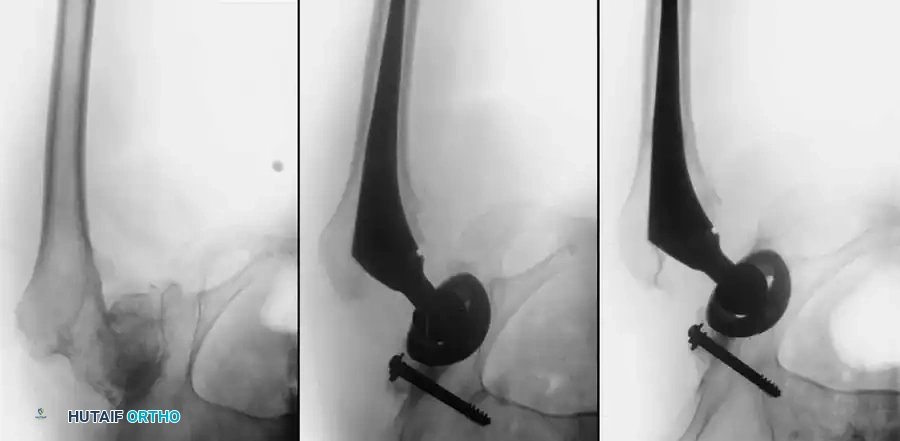

Radiographic Case Examples: Osteonecrosis and Complex Femoral Reconstructions

Advanced osteonecrosis with subchondral collapse and secondary arthritis.

Intraoperative imaging showing retained fibular graft from a previous joint-preserving procedure.

Use of a high-speed burr to clear the intramedullary canal of sclerotic graft remnants.

Fluoroscopic confirmation of proper broach alignment after graft removal.

Final seating of a cementless femoral stem in optimal neutral alignment.

Postoperative radiograph confirming excellent fit and fill of the femoral component.